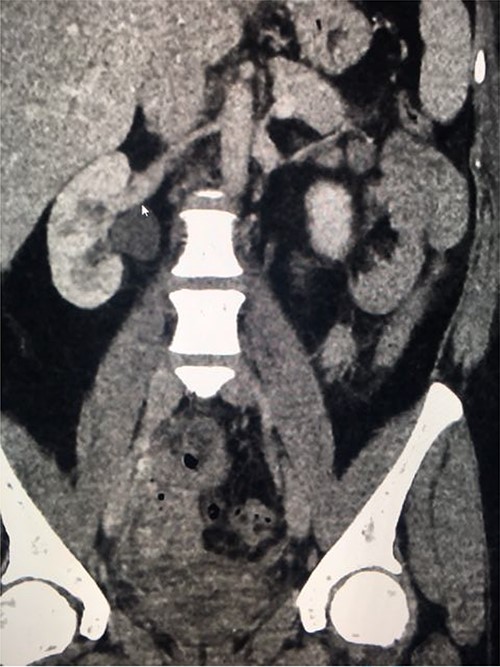

Computed tomography (CT) with urographic phase imaging demonstrated a right distal ureteric injury with leakage of urine into the pelvis and fistulation into the vagina (Figs 1 and 2). A diverting right percutaneous nephrostomy was inserted in the interventional radiology (IR) suite. An antegrade ureterogram at the same time demonstrated a complete discontinuation of the ureter which appeared retracted (Fig. 3).

Coronal delayed phase CT urogram showing pooling of contrast in the pelvis.